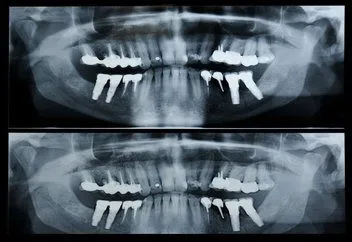

A panorex is a very impressive piece of imaging machinery in that it is capable of identifying many issues and structures that a normal x-ray is not. Initially you will sit in a chair with your chin on a small ledge. Once positioned in the machine, it will rotate around your entire head taking a full 360 degree view of the teeth, head, sinuses and bones.

The ability to view the full structure of your head as a whole is very informative to the dentist. It will allow us to see any potential problems and make sure that everything is functioning as it should be. The panorex is capable of viewing specific types of structural problems, infections or asymmetry among many others.